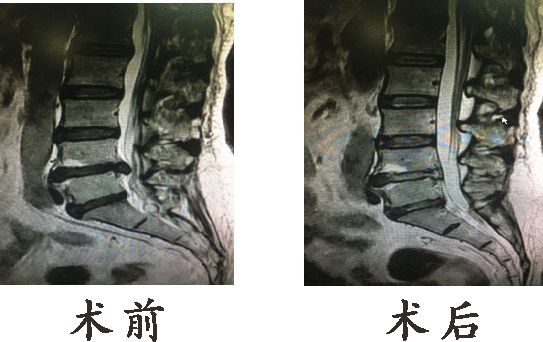

●椎间孔镜髓核摘除术

椎间孔镜是一个配备有灯光的管子,它从病人身体侧方或侧后方进入椎间孔,在安全工作三角区实施手术。使用各类抓钳摘除突出组织、镜下去除骨质、射频电极修复破损纤维环。手术创伤小:皮肤切口仅7mm,如同一个黄豆粒大小,术后仅缝1针。

【Kambin-安全三角】可经椎间孔部位的安全三角区域进行内镜手术。

手术入路的选择:适应症:

1、椎间盘突出、椎间孔骨质增生引起的神经根性疼痛,经保守治疗效果不佳者。

2、中央型、侧旁型、外侧型、极外侧型的腰椎间盘突出者。

3、腰椎椎间孔狭窄及腰椎管狭窄者。

4、椎间盘突出开放手术后复发者。